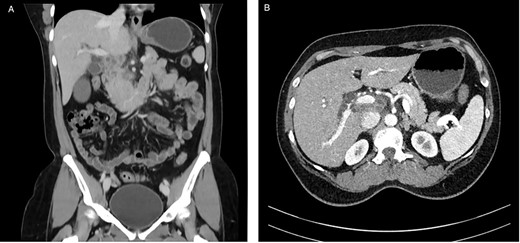

A 53-year-old female of Indian origin, resident in Switzerland for 20 years, presented with diffuse abdominal pain, nausea and meteorism in the primary care consultation. After an initial workup with blood tests and ultrasound (US), a CT of the abdomen was performed (Fig. 3), which revealed enlarged, central necrotic lymph nodes adjacent to the common bile duct (CBD) and the pancreatic head. The enlarged lymph nodes caused an obstruction of the CBD. The patient was referred to our institution for further diagnostic tests.

CT with contrast (A) coronal view and (B) axial view: cystic solid mass in the region of the hepatic hilus with unclear association to the head of the pancreas.